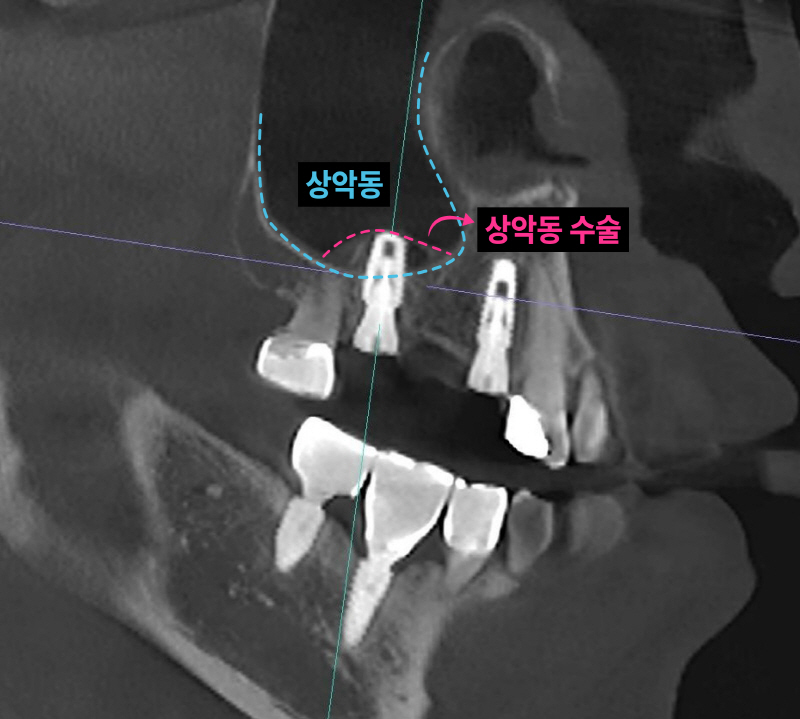

이미 신경치료된 치아 뿌리 끝에 염증이 잡혀있고 브릿지 아래로 2차충치가 크게 생겨서 임플란트로 치료 계획을 정했습니다. 임플란트 2개를 심고 치아 머리(크라운) 3개를 만듭니다. 여러 개의 임플란트를 심을 때 꼭 개수대로 임플란트를 심을 필요는 없습니다. 과거에는 발치, 상악동 수술, 임플란트를 전부 기다리며 나눠서 진행했는데 시간이 너무 오래 걸립니다. 저는 최대한 치아가 없는 기간을 단축시키기 위해서 치아를 뽑고(발치) 동시에 임플란트를 심으며 뼈가 없는 경우 상악동 수술을 동시에 진행합니다.

남아있는 잇몸뼈가 5-6mm 정도입니다. 저는 이런한 경우 덴샤버라는 특수한 기구를 이용해서 가능한 빠르면서 안아프고 쉽게 상악동 수술을 시행합니다. 항상 CT를 통해 환자분들께 정확하게 수술된 모습을 보여드립니다.